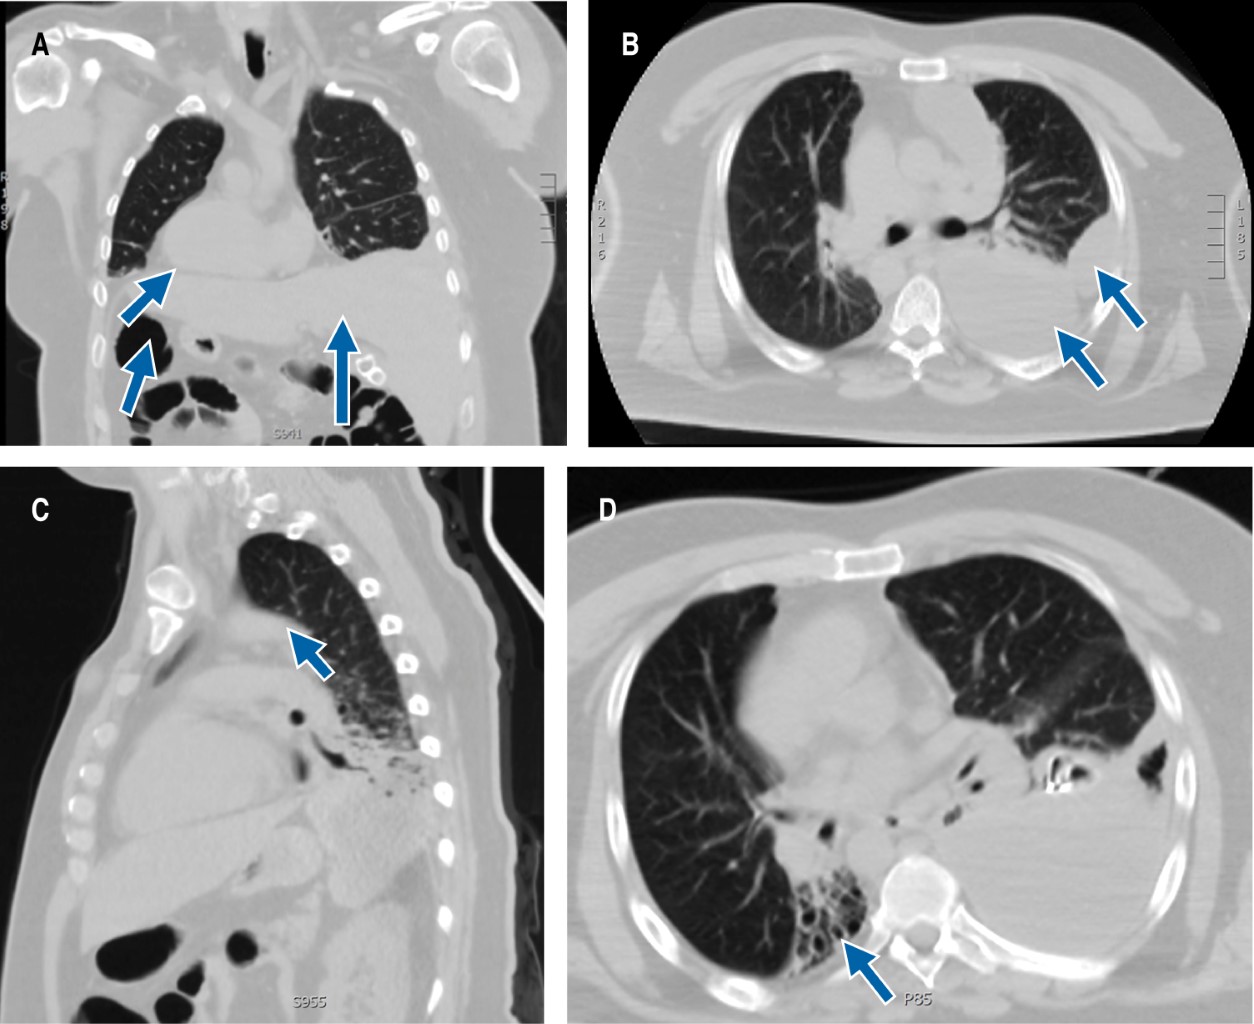

Paciente masculino de 40 años de edad, casado, sin hijos, con antecedente de hipertensión arterial esencial de seis meses de diagnóstico en tratamiento con ARA-II (antagonistas de los receptores de la angiotensina II), adecuado control. Antecedentes de sinusitis crónica de 31 años de diagnóstico sin tratamiento; se informa portador de situs inversus totalis a los nueve años de edad. Hospitalizaciones recurrentes secundarias a neumonías adquiridas en la comunidad, que hasta el momento no habían condicionado alguna complicación. Inició padecimiento con fiebre no cuantificada, disnea de pequeños esfuerzos y tos; por ello, es ingresado al área de urgencias. Se realizaron estudios de laboratorio que reportaron ligera leucocitosis a expensas de neutrofilia, incremento de reactante de fase aguda (PCR 50.04), el resto de paraclínicos en valores de referencia de acuerdo con el laboratorio. La radiografía de tórax (no se cuenta con ella) mostró dextrocardia, atelectasia y área de condensación en la base de hemitórax derecho; no respeta plano anatómico, por lo que se considera como imagen atípica. Se realiza prueba rápida para SARS-CoV-2 que resulta negativa. Se solicita tomografía axial computarizada (TAC) contrastada de tórax y abdomen con reporte de situs inversus totalis (Figura 1A), masa en base izquierda y en mediastino anterior (Figura 1B y 1C), con ligera captación de contraste, además de bronquiectasias bibasales (Figura 1D). Con base en los resultados de laboratorio e imagen, se brinda tratamiento para neumonía adquirida en la comunidad (NAC), PSI (pneumonia severity index) de 70 puntos clase III de riesgo, con doble esquema de antibiótico. Debido a que la clínica, principalmente la tos, no cedía se realizó cultivo de expectoración, con crecimiento a los siete días de Granulicatella elegans; se mantiene esquema de tratamiento instaurado por diminución de 50% del valor inicial de PCR. Se concluye curso de derrame pleural complicado a expensas de loculaciones; se colocó sonda endopleural para tratar de drenar derrame sin éxito alguno, sin obtener tampoco muestra para envío a citológico y citoquímico de líquido pleural. Se trasladó al área de cirugía de tórax para decorticación por derrame pleural complicado, de probable origen paraneumónico por infecciones de repetición, secundario a discinesia pulmonar con eliminación inadecuada del moco ciliar que condiciona la encapsulación.